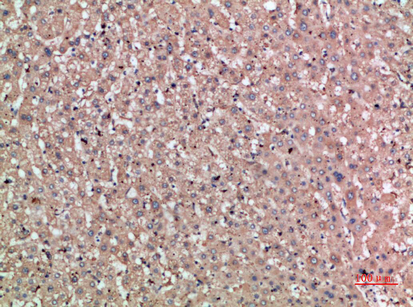

Anti-TAT AntibodyA98309

ApplicationsELISA, ImmunoHistoChemistry

ReactivityHuman, Mouse, Rat

- SizePrice